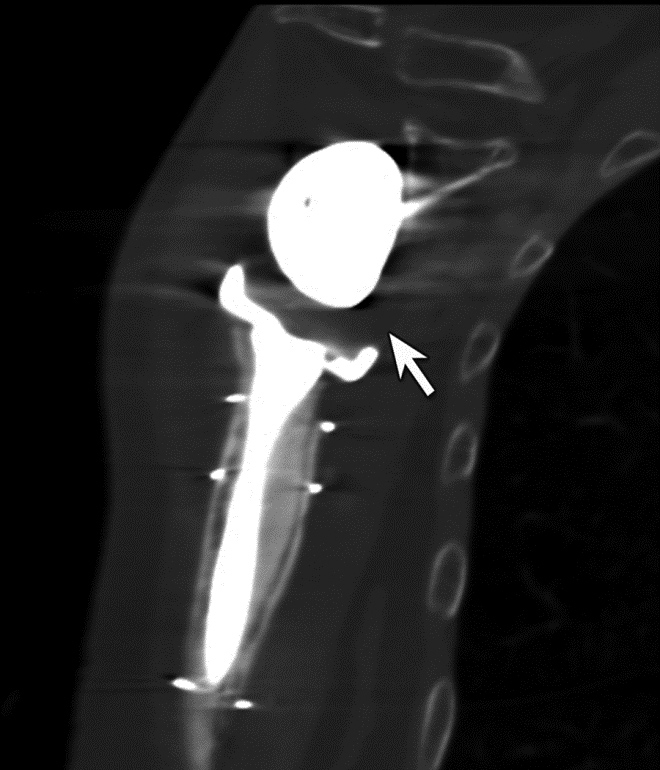

Just as with the immediate post-operative setting, CT is the modality of choice for evaluating complications related to spinal fusion. Screw fracture may occur in up to 25% of patients (Figure 13) (Ohashi, 2009; Lonstein, 1999). As with all cases of hardware failure, the imaging findings should be correlated with patient symptoms as not all hardware complications relate to current clinical symptoms. CT can be useful for the detection of polyethylene dislocation, which may occur in shoulder, hip and knee arthroplasties, and may be difficult to detect on radiographs (Figure 14) (Clarke, 2004).

Polyethylene Liner Displacement. Sagittal multiplanar reformation of reverse total shoulder arthroplasty demonstrates posteriorly displacement of low attenuation polyethylene liner relative to the humeral component and glenosphere in patient with limited range of motion.